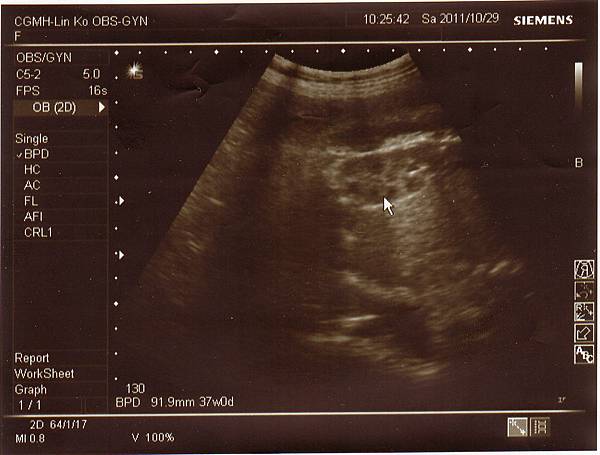

希望她可以到11月再出生,今天除了例行性產檢外,

還到三樓產房做胎心音監測,

1029-3.jpg